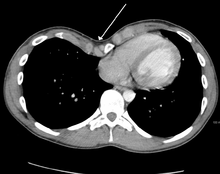

Many scales have been developed to determine the degree of deformity in the chest wall. Most of these are variants on the distance between the sternum and the spine. One such index is the Backer ratio which grades severity of deformity based on the ratio between the diameter of the vertebral body nearest to xiphosternal junction and the distance between the xiphosternal junction and the nearest vertebral body.[19] More recently the Haller index has been used based on CT scan measurements. An index over 3.25 is often defined as severe.[20] The Haller index is the ratio between the horizontal distance of the inside of the ribcage and the shortest distance between the vertebrae and sternum.[21]

Pectus excavatum requires no corrective procedures in mild cases.[24] Treatment of severe cases can involve either invasive or non-invasive techniques or a combination of both. Before an operation proceeds several tests are usually to be performed. These include, but are not limited to, a CT scan, pulmonary function tests, and cardiology exams (such as auscultation and ECGs).[2] After a CT scan is taken the Haller index is measured. The patient's Haller is calculated by obtaining the ratio of the transverse diameter (the horizontal distance of the inside of the ribcage) and the anteroposterior diameter (the shortest distance between the vertebrae and sternum).[25] A Haller Index of greater than 3.25 is generally considered severe, while normal chest has an index of 2.5.[21][26][27] The cardiopulmonary tests are used to determine the lung capacity and to check for heart murmurs.